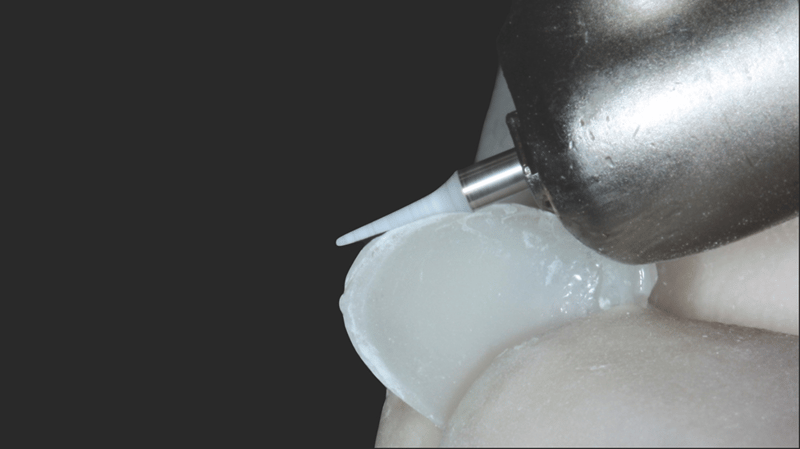

- Composite Placement: Transcend composite in B1D shade was placed starting 2/3 up from the incisal edge, gradually thinning towards the gingival area. The Universal Body (UB) shade was applied near the gingival 1/3, with final layers using Enamel White (EW) and a small amount of UB at the gingival margin for natural blending.